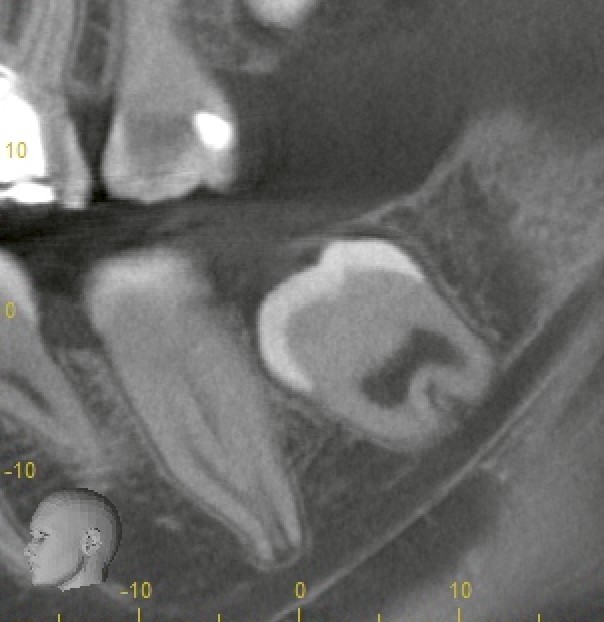

今回の患者様は上下左右4本すべてが埋伏している状態で、年齢は20歳未満。

レントゲンおよびCTを確認すると、歯根がまだ完成していない「未完成根(根尖未完成)」の状態でした。

今回の患者様はまだ20歳前であることから、歯根の先端(根尖)は未完成で、レントゲンでも明瞭に確認できました。